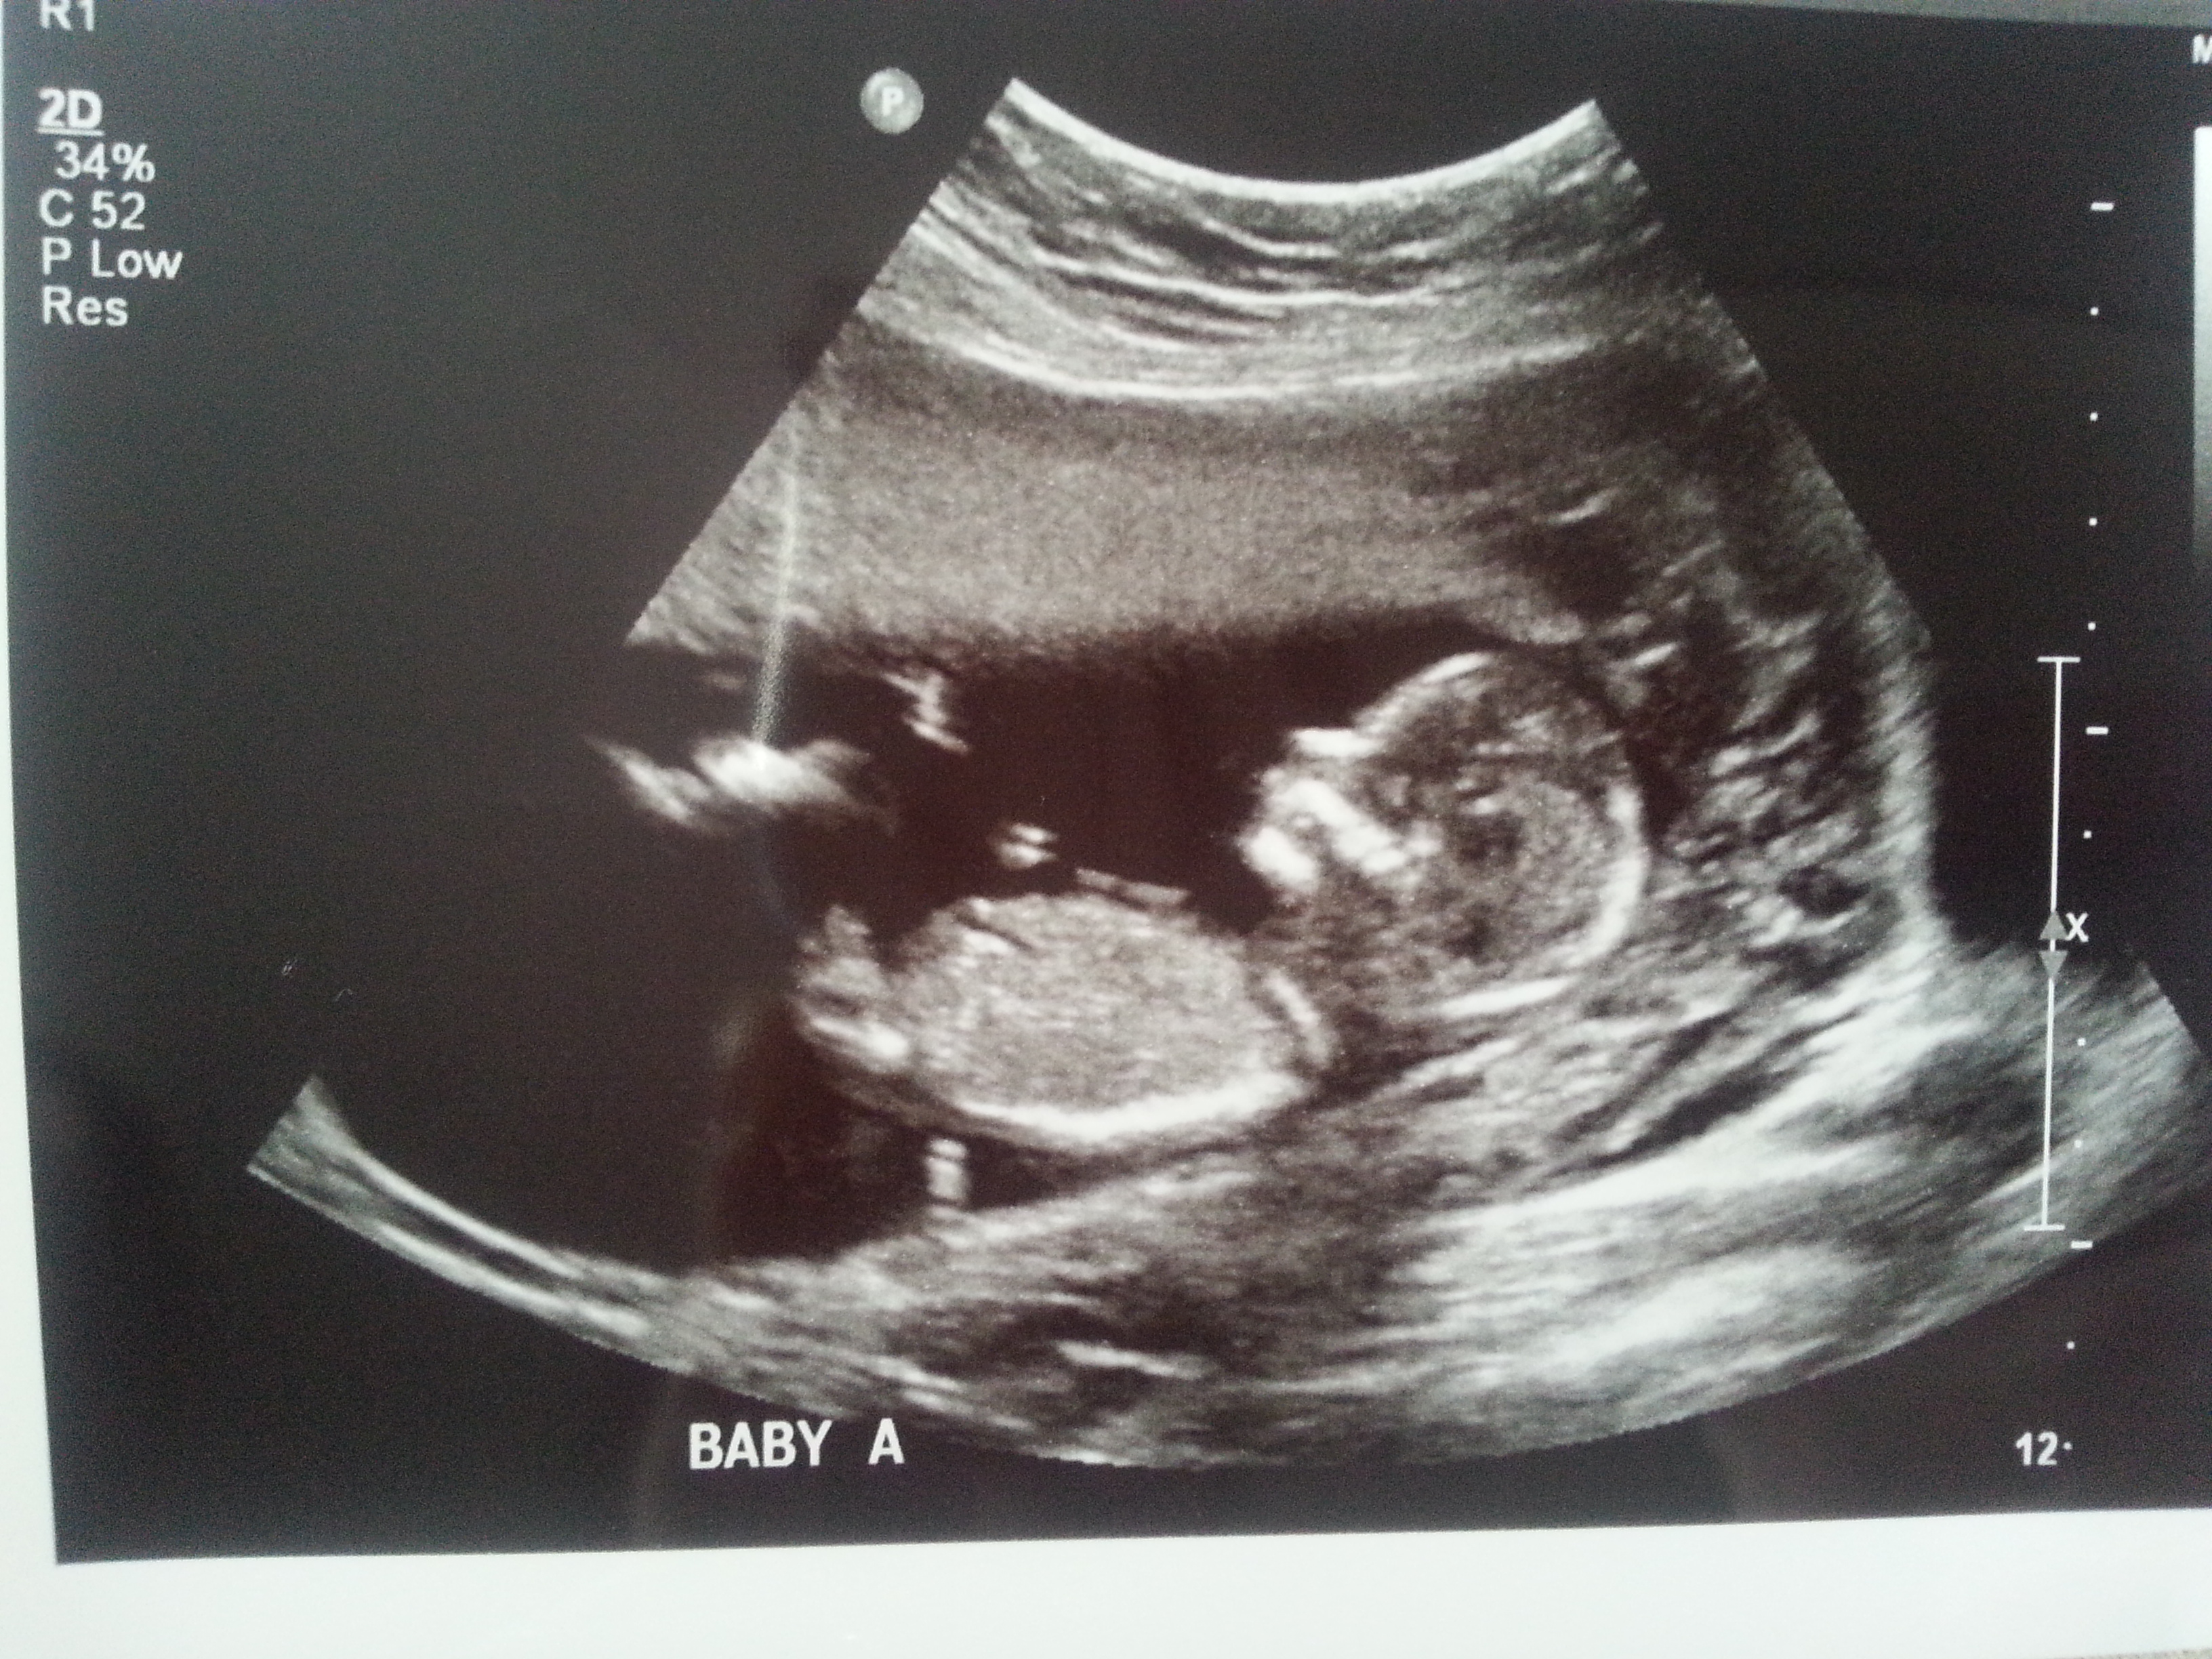

I was 12weeks 6 days and measuring 13weeks 3 days.

Attachment 23433

Maybe boy/girl. Not the best shots though!

I think B is a boy and A is a girl.

I think B is a boy, A could go either way but I lean boy.

I think I'm seeing a very boyish nub for baby B. Baby A not as sure. I hope that's your girl! Congrats and good luck!

On your second pic of baby B I'm looking at the little line between the legs that's almost sticking straight up.... very boyish "angle of the dangle".